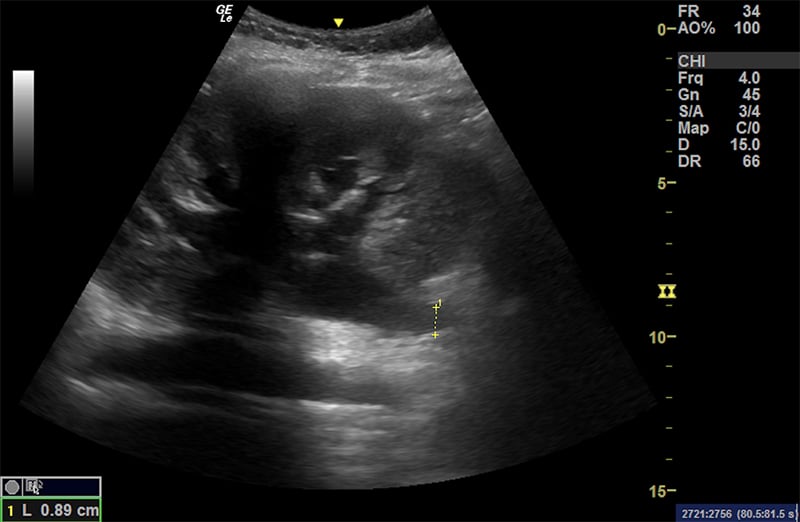

Figure 37. A normal greatest vertical pocket of amniotic fluid. Note the calipers measuring the deepest pocket of amniotic fluid not containing any fetal parts.

- After scanning the entire uterine cavity systematically (mowing the lawn), find and measure the single deepest pocket of anechoic amniotic fluid perpendicular to the bed with no fetal parts present. The probe marker should be pointing to the patient’s head.

- Normal ranges from 2cm – 8cm